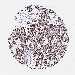

CANCER LUNG CANCER Show tissue menu

Lung cancer

Human cancer

Lung adenocarcinoma

Lung squamous cell carcinoma